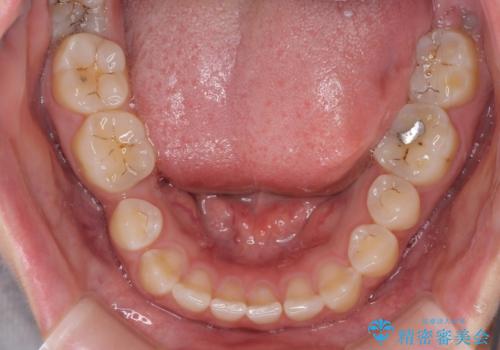

- 隙間の多い歯列や傾斜した奥歯、むし歯の酷い残存乳歯を気にして来院された患者様です。

歯列はワイヤー矯正にて改善することとしましたが、上下歯列にも隙間があったので、舌の突出癖を改善するトレーニングを徹底的に行うこととしました。

傾斜した下顎の奥歯は、矯正治療にてまずは歯軸を改善させ、隙間が閉じられるようであればそのままに、閉じられないようであればインプラント治療を行うこととしました。

上顎のむし歯の酷い残存乳歯は抜歯をし、矯正治療の途中でインプラントを埋入、矯正治療後に補綴治療を行うこととしました。